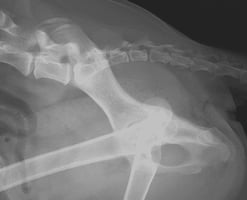

Ocular surface diseases in dogs are frequently encountered in routine ophthalmology consultations. These include ulcerative keratitis, pigmentary keratitis and keratoconjunctivitis sicca, and are typically seen in brachycephalic dogs. The underlying cause is their abnormal conformation: large palpebral fissures (macroblepharon), prominent globes and corneal exposure due to shallow orbits, medial lower eyelid/canthal entropion and associated trichiasis, as well as caruncular trichiasis (Figure 1). Together, these conditions are also known as brachycephalic ocular syndrome (BOS) (Nutbrown-Hughes, 2021; Costa et al., 2021; Palmer et al., 2021; Sebbag and Sanchez, 2023). Although medical management can alleviate the clinical signs associated with this anatomical abnormality, it is usually insufficient, leading to the progression and worsening of ocular surface diseases. Medial canthoplasty is a surgical technique that corrects the anatomical abnormalities present in brachycephalic dogs, significantly improving overall ocular surface health.

When performed appropriately, the medial canthoplasty procedure reduces the length of the palpebral fissure, enhancing globe protection by the eyelids, allowing for a complete blink and improving tear film distribution over the cornea (Figures 4D, 5D, 6D and 7). This helps reduce excessive evaporation of the tear film and minimises corneal exposure (Figures 4E, 4F, 5E and 5F). Medial entropion is resolved by removing the in-rolling skin and releasing the tension from the medial canthal ligament. Removing the caruncles eliminates caruncular trichiasis.

Some corneal changes associated with chronic corneal trauma and irritation (such as corneal fibrosis, vascularisation and pigmentation) have been reported to stop progressing and even improve following medial canthoplasty and topical treatment (Figures 6B, 6C, 6E, 6F and 8) (Allgoewer et al., 2016). It is common for these patients to be started on long-term treatment with topical lacrimostimulants/immunomodulators, such as cyclosporin A or tacrolimus, which have been shown to reduce corneal pigmentation and inflammation, thereby enhancing corneal transparency and improving vision (Crasta et al., 2023).

Medial canthoplasties have a significant impact on the conformation of patients who undergo this procedure, resulting in considerable changes to their appearance (Figures 6A, 6D, 9A and 9B). While this intended outcome does not influence the clinical decision to choose this surgical technique when indicated, it does significantly affect the owners. Therefore, it is important to ensure that owners are fully informed about the cosmetic results of the procedure.